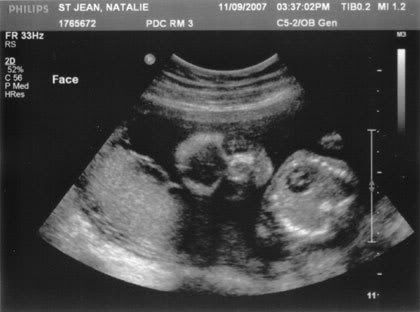

His sweet little face

Proof it really IS an alien in my belly ;)

The first glance was the baby curled up in a ball, which made me worry, but he didn’t stay there for long. For the first 10 minutes or so she was measuring the baby’s head, arms, heart, etc, in addition to checking on the position of my placenta and how my cervix was doing. I was trying to enjoy it, but at the same time I really wanted her to hurry up and get down to the important part. lol We kept seeing the baby’s hand all outstretched, all five little fingers. Looks like long little fingers, just like mama. :mushy: It was hard to get my bearings straight, as she was moving the U/S wand around so much to get the best angle for pictures. Baby was definitely constantly moving though… she was kind of talking to him, “Come on baby, move a little…” She’d wiggle the wand around a little as if trying to convince him to move around.